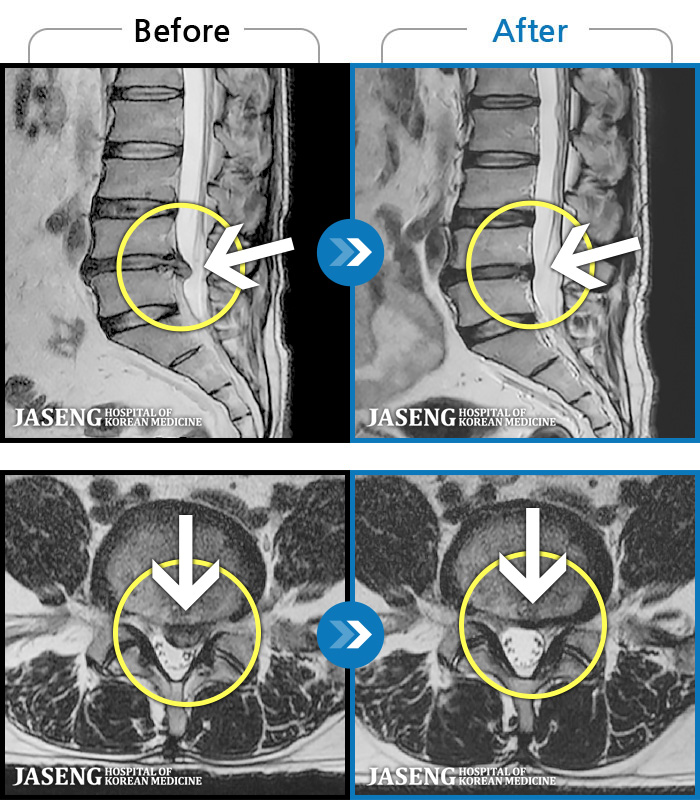

MRI로 보는 치료결과

1,228건의 MRI 전후 사진으로 터진 디스크 흡수 사례를 확인하세요.

[해운대] 23.09.18~25.01.27

※ 환자분에게 사전 동의를 받아 동일 조건에서 촬영되었으며, 개인에 따라 치료 후 부작용이 발생할 수도 있으니 사전에 의료진과 상담 후 치료를 진행하시기 바랍니다.